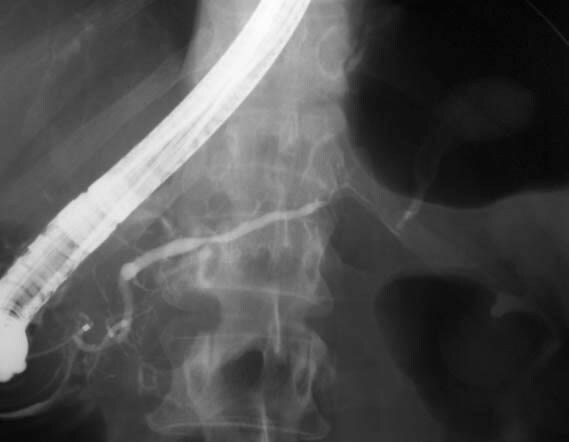

Picture above is of a patient who has been in a motor cycle accident who has also had heavily drinking problems in the past. The thin white line in the image is of a growth off the pancreas.